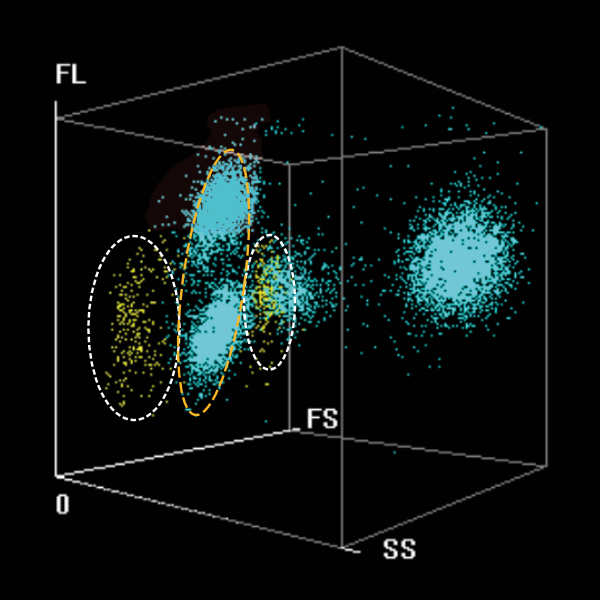

Flag Towards Precise Screening of Infectious Mononucleosis (IM)

DIFF 3D scattergram

3D Scattergram of typical infectious mononucleosis

Alert precisely for reactive lymphocytosis caused by infectious mononucleosis

through the distribution characteristics of scatter plots

Reactive Lymph-IM?